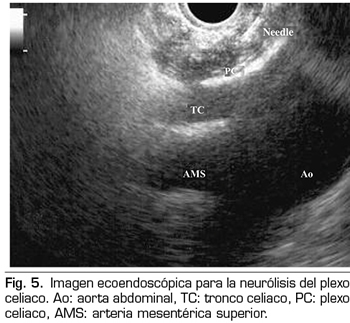

NEURÓLISIS ECOENDOSCÓPICA DEL PLEXO CELIACO

La ecoendoscopia ofrece la ventaja de una mayor visualización del plexo celiaco a corta proximidad, permitiendo una mayor precisión y seguridad en la administración del agente neurolítico y evitando la inyección en estructuras vasculares mediante el uso del Doppler (37) (Figura 5). No obstante, los trabajos que apoyan la neurólisis ecoendoscópica, considerada al igual que la técnica percutánea como una terapia de rescate, están limitados a estudios retrospectivos no controlados (38). Pauli y cols. publicaron un metanálisis que concluye que esta técnica consigue una reducción del dolor del 80 % en pacientes con cáncer de páncreas (39). Algunos estudios muestran un ligero descenso en el consumo de opioides, pero sin una fuerte evidencia científica.

En cuanto a los efectos adversos, se limitan a una serie de publicaciones retrospectivas y series de casos, estando descritos la hipotensión (11 %), la diarrea (18 %) y el dolor abdominal transitorio (1,5 a 8 %) (37). Teóricamente, esta técnica es más segura, con su abordaje anterior a través de la pared gástrica y paso directo de la aguja al plexo visualizando los vasos, sin tener que atravesar el espacio retrocrural (41). Aun así, también se han publicado complicaciones fatales con esta técnica. Gimeno-García y cols. (42) describieron la primera complicación de trombosis y vasoespasmo de la arteria celiaca que produjo una isquemia multiorgánica y la muerte del paciente. Desde entonces esta complicación se ha publicado en otros 2 trabajos, que también acabaron en muerte (43,44). Otros efectos adversos descritos son el sangrado retroperitoneal y 2 casos de paraplejia.

Dentro de las contraindicaciones relativas a esta técnica se encuentran: la presencia de varices gástricas o esofágicas −ya que aumentan el riesgo de sangrado−, una anatomía desestructurada, la invasión tumoral directa del plexo, y las malformaciones congénitas del tronco celiaco o de la arteria mesentérica superior.